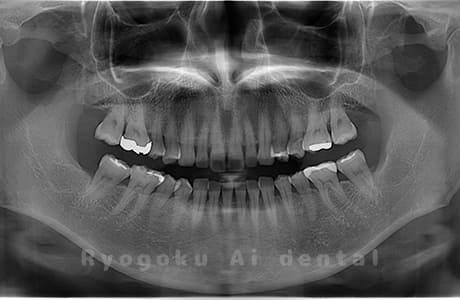

Case02

-

- 原因

- 下顎の水平埋伏智歯

- 治療内容

- 下顎の水平埋伏智歯を抜歯

<リスク・副作用>

手術後は痛み、腫れ、痺れなどの副作用が生じる場合があります。